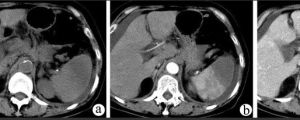

2.CT表現:

①梗死灶多發生於脾前緣處近脾門的方向,平掃時為低密度區。

②梗死灶呈三角形或楔形、底近脾的外緣.尖端面向脾門。

③增強掃描顯示更為清楚.脾密度增高而梗死灶不增強,對比更好。

①脾梗死灶在急性期(8天以前)呈低密度區,不強化;在慢性期(15-28天)則密度逐漸恢復正常,由於已出現瘢痕組織,瘢痕收縮可引起脾臟出現收縮變形情況。

⑤若整個脾臟梗死.則在增強掃描時,整個脾臟呈不強化現象,只有脾包膜有增強現象。